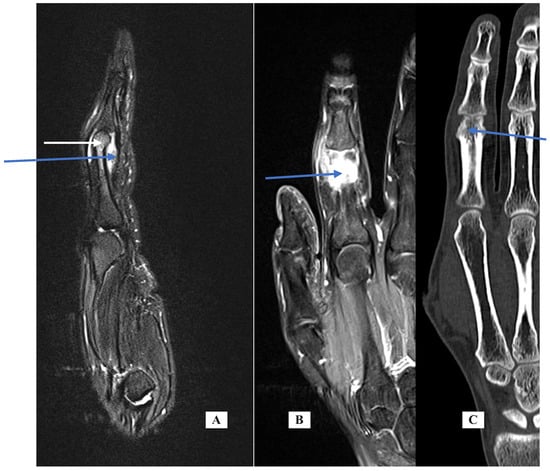

Case 4: A 12-year-old female presented with a 2-month history of right F4 PIP pain and stiffness. At the time of her presentation in January 2021, she had moderate swelling of her finger, mild local warmth, no erythema, PIP motion of 25 to 70 degrees, and local tenderness. X-rays showed a periosteal reaction of the distal P1 (Figure 3, left). Labs for inflammation were normal. The MRI scan (Figure 3, center, T1 with fat suppression) showed bone marrow edema enhancement, synovitis of the PIP joint, tenosynovitis of flexor and extensor tendons, and erosion irregularity of the volar distal cortex under the P1 condyle. The report noted that the images were consistent with osteomyelitis. She was referred to a pediatric rheumatologist for evaluation. His presumed diagnosis after evaluation was inflammatory or infectious disease. He recommended additional labs including serology for hepatitis, creatine phosphokinase (CPK), anti-nuclear antibody (ANA) using immunofluorescence assay (IFA) methodology, and urinalysis, all of which were negative.

At that point, the images were reviewed with an orthopedic tumor specialist (AP), who suggested evaluation with a CT scan. The images (Figure 3, sagittal view, right) showed a small lucent cortical lesion 4 mm in length with central calcification and a periosteal reaction of the proximal phalanx consistent with osteoid osteoma (OO). She denied increased symptoms at night or pain relief with NSAIDs. She was taken to surgery using a volar approach and the lesion was treated with curettage and with local burring, but no additional adjuvant treatment. Pathology was consistent with OO and the margins were clear. Her pain resolved and the swelling and motion improved. At her last appointment, her X-rays had normalized.

Case-specific comment: The plain X-rays did not reveal the diagnosis that became apparent only with the CT scan. In retrospect, the periosteal reaction seen on the plain X-rays was a result of the osteoid osteoma in the distal metaphysis. Since there is no periosteum in the metaphysis, the inflammatory reaction stimulated periosteal new bone formation more proximally along the diaphysis. This periosteal new bone resorbed after removal of the nidus. Typically, the nidus is well-seen in MRI, but perhaps because of the small lesion and the resolution of the images, the diagnosis was not made via MRI but seen clearly on the CT scan.

Figure 3. Case 4—X-ray lateral of the finger (A) demonstrating cortical thickening; MRI sagittal of the finger (B) demonstrating bone marrow edema distal P1, irregularity of the distal cortex (blue arrow) and generalized soft tissue swelling; CT sagittal of the finger (C) demonstrating lucency with a central calcification consistent with nidus.